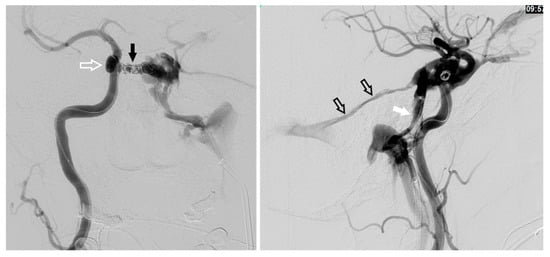

Figure 2. The anterior facial vein (solid arrow), angular vein (black arrow), and superior ophthalmic veins (white arrow) are shown.

Figure 3. The middle temporal vein (solid arrow) and its connection (open arrow) with the SOV are demonstrated.